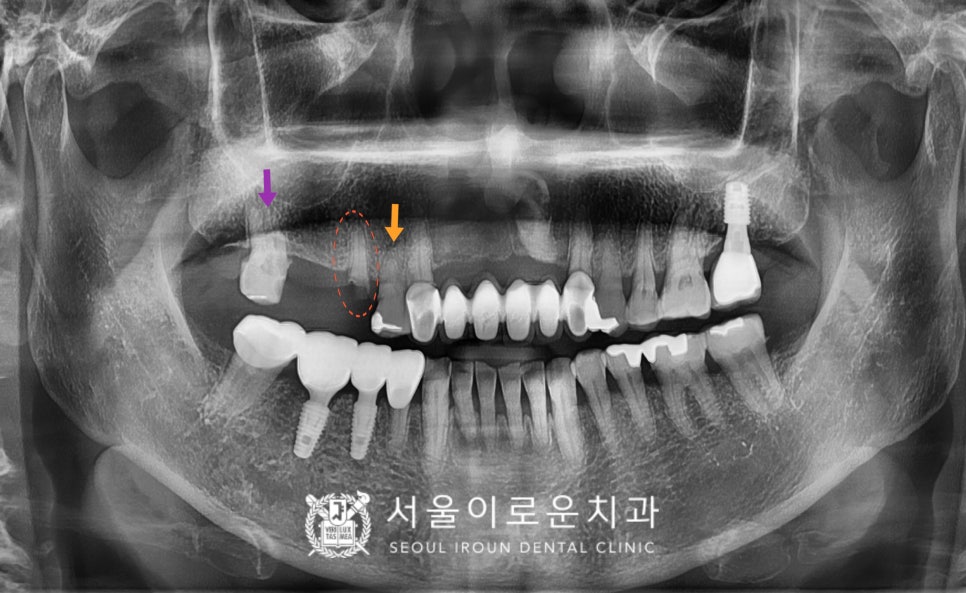

정밀한 검사를 위해

파노라마 사진을 촬영하여

확인해 보았더니

✅ 빨간색 동그라미 표시의

위턱 오른쪽 두 번째 작은 어금니(#15)는

충치로 인해 뿌리만 남아 있는

상태였는데요.

이 경우 살려 쓰기에는

어려움이 있어 발치를 해야 하는

상황이었습니다.

✅ 그리고 보라색 화살표 표시의

위턱 오른쪽 두 번째 큰 어금니(#17)는

충치가 깊어 신경치료 후

크라운 수복이 필요했습니다.

✅ 더불어 주황색 화살표 표시의

위턱 오른쪽 첫 번째 작은 어금니(#14)의

기존 아말감 되어 있는 부위에도

수복물 하방으로 이차 충치가 관찰되어

치료가 필요했는데요.

다행히 신경까지 충치가 진행되지 않아

신경치료는 피할 수 있었지만